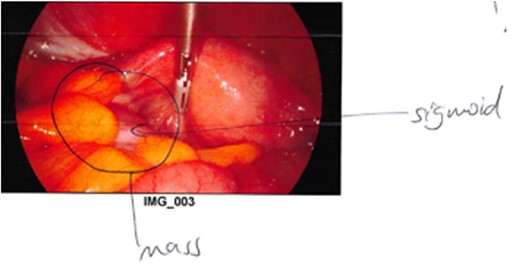

Non-operative management with broad-spectrum IV antibiotics, bowel rest and fluids was trialled. Despite initial clinical improvement with a reduction in pain and down-trending inflammatory markers the patient was once again febrile on day 3 of her admission with plateauing of the inflammatory markers and ongoing pain. A progress CT scan (Fig. 2) showed an unchanged adnexal collection now with sigmoid thickening. Given the findings and lack of clinical improvement, the patient proceeded to have a laparoscopic anterior resection and en bloc left salpingo-opherectomy. Intra-operatively (Figs 3 and 4), the fistula between the sigmoid colon and the left salpinx was very clearly demarcated. Histology confirmed acute diverticulitis locally perforating into the left salpinx and ovary and forming an abscess. An uneventful recovery followed.

Intraoperative photograph demonstrating the colo-salpingeal fistula.